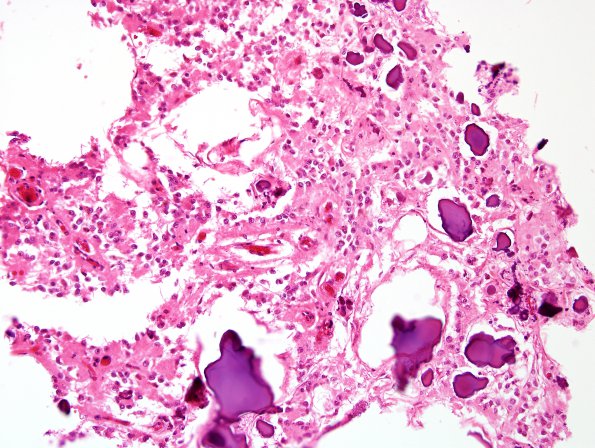

4A2,3 Calcium concretions are admixed with pineocytes and their processes (H&E)